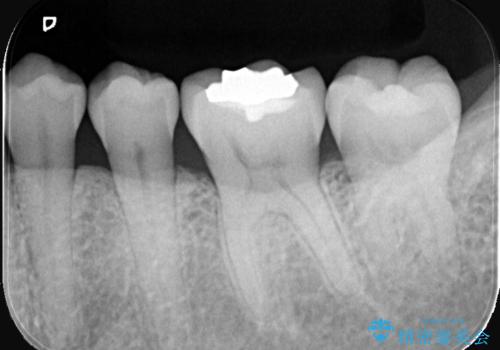

歯が欠けたことによるものか、もしくは以前装着された修復物の不適合が原因と考えられますが、銀歯(メタルインレー)と歯との間に大きな段差が認められ、汚れが溜まりやすい状態となっていました。

このような状態では、修復物の内部で虫歯が進行している可能性が高いため、治療が必要と判断しました。